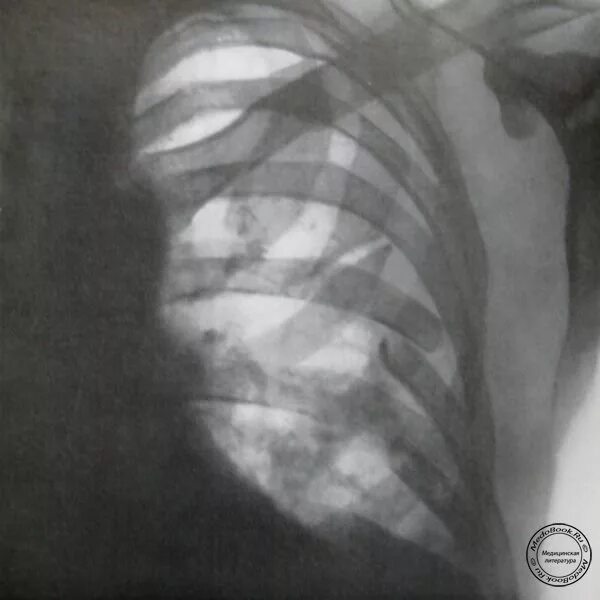

Множественные ребра